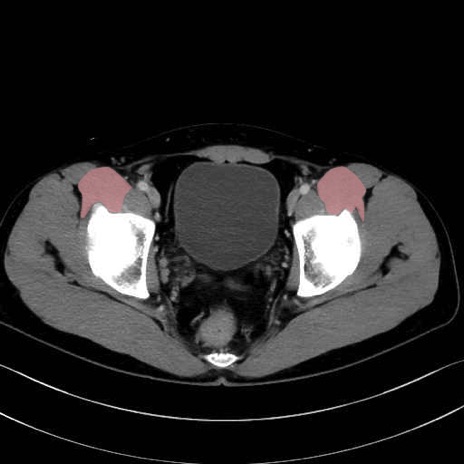

腸骨筋 (Iliacus)